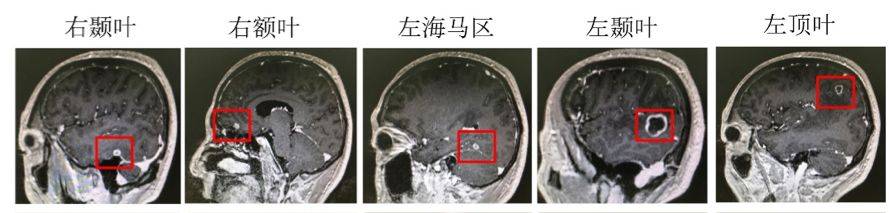

头颅双倍剂量增强MRI(2019.1.22)

双侧颞叶、左侧海马区、左侧顶叶、右侧额叶可见多发结节样强化灶,考虑转移瘤。

图3. 头颅双倍剂量增强MRI(2019.01.22)